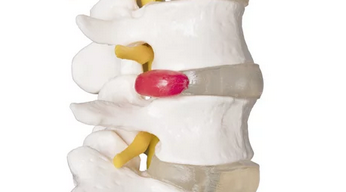

허리디스크(추간판탈출증)는 척추 사이의 디스크(추간판)가 탈출하여 신경을 압박하면서 통증과 신경증상을 유발하는 질환이다.

허리디스크는 척추 뼈 사이에 위치한 디스크가 탈출하여 신경을 압박하는 질환이다.

주로 요추(허리) 부위에서 발생하며, 심한 경우 다리 저림과 마비 증상까지 동반될 수 있다.